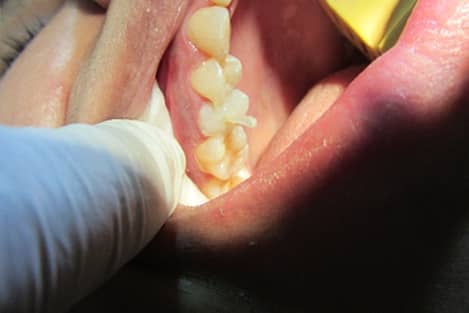

Post n Core